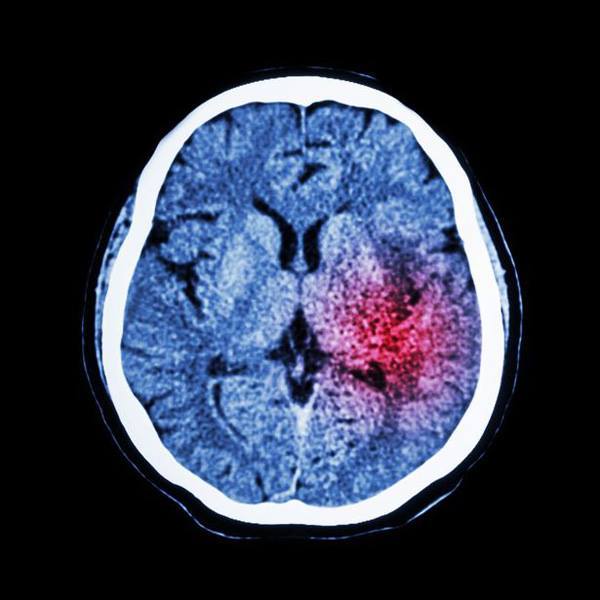

Qua các xét nghiệm ban đầu, bác sĩ nghĩ rằng người phụ nữ lên cơn động kinh nhưng quét CT cho thấy có máu chảy giữa hộp sọ và não, cho thấy đây thực sự đã đột quỵ. Họ chẩn đoán người phụ nữ bị xuất huyết dưới nhện - một sự chảy máu đột ngột vào khoang trống (khu vực dưới màng nhện) ở giữa não và lớp màng bao phủ não.

Quét CT cho thấy các bản khắc điển hình được nhìn thấy sau đột quỵ